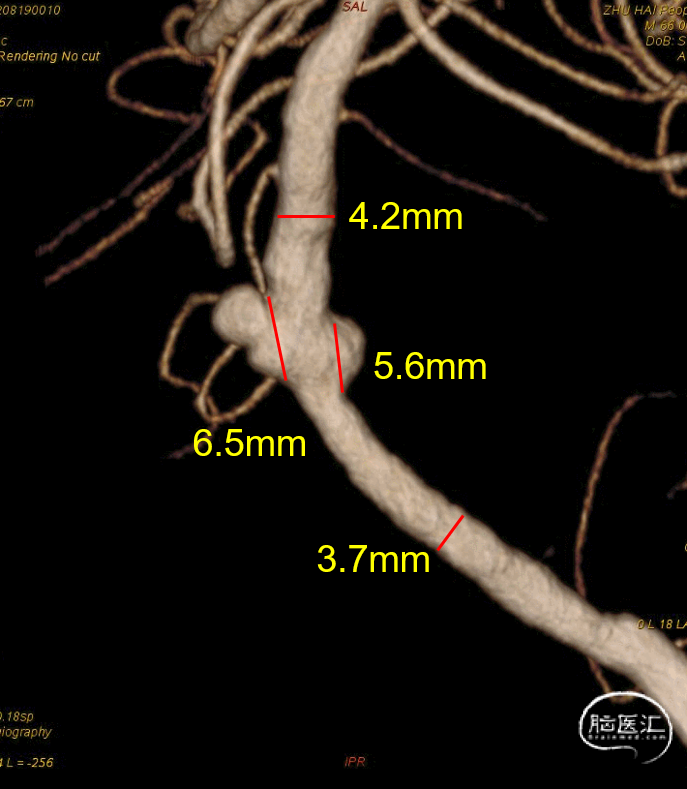

通过3D工作位测量出基底动脉瘤瘤颈最宽处:6.5mm;载瘤动脉尺寸:近端直径3.7mm,远端直径4.2mm。

3D重建